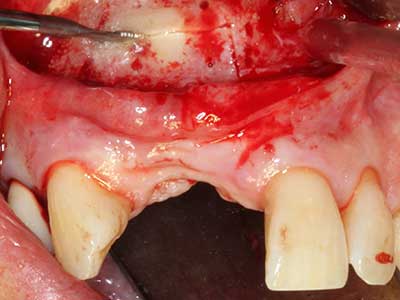

Aplicación: Preparación cerca del nervio

Como ya se ha mencionado, en el ámbito de la odontología conservadora también existen áreas en las que está indicada la cirugía piezoeléctrica. El uso de insertos de trabajo especiales facilita la representación del ápice radicular y, sobre todo en el área de los premolares inferiores y superiores, protege mejor los nervios y las mucosas del seno maxilar. En el caso de un cierre apical no estanco, los insertos de diamante acodados preparan de forma exacta y selectiva la cavidad de resección para el material de relleno retrógrado de la raíz. Gracias a la técnica de ultrasonidos, los insertos pueden presentar un diseño muy estilizado, lo que mejora la visión global y el tamaño de la cavidad de acceso. De este modo, en esta indicación, el uso de la cirugía por ultrasonidos se encuentra entre los métodos estándar para una apicectomía (Del Fabbro, Tsesis et al. 2010, Scarano, Artese et al. 2012).

Aplicación: Apicectomía

Si es preciso realizar intervenciones quirúrgicas en las que el hueso está en contacto directo con estructuras sensibles, como son los vasos sanguíneos o los nervios, los instrumentos rotativos presentan un enorme potencial de provocar lesiones iatrogénicas. Así, precisamente en la representación de nervios después de una lesión iatrogénica, o en el transcurso de la lateralización de un nervio para resecciones, reconstrucciones o incorporación de implantes, los equipos piezoeléctricos pueden resultar muy útiles para preparar la tapa ósea y retirar las partes de tejido duro cercanas al nervio (fig. 17-20). Por lo general, un ligero contacto del cordón nervioso con el inserto piezoeléctrico no tiene consecuencia alguna; ahora bien, un procedimiento poco cuidadoso con movimientos tipo sierra o piezas de trabajo sobre la base ósea aún existente puede provocar lesiones nerviosas temporales o incluso permanentes. Con todo, el riesgo de sufrir una lesión de este tipo se considera significativamente inferior que en los casos en los que se utilizan sierras y fresas (Pereira, Gealh et al. 2014).